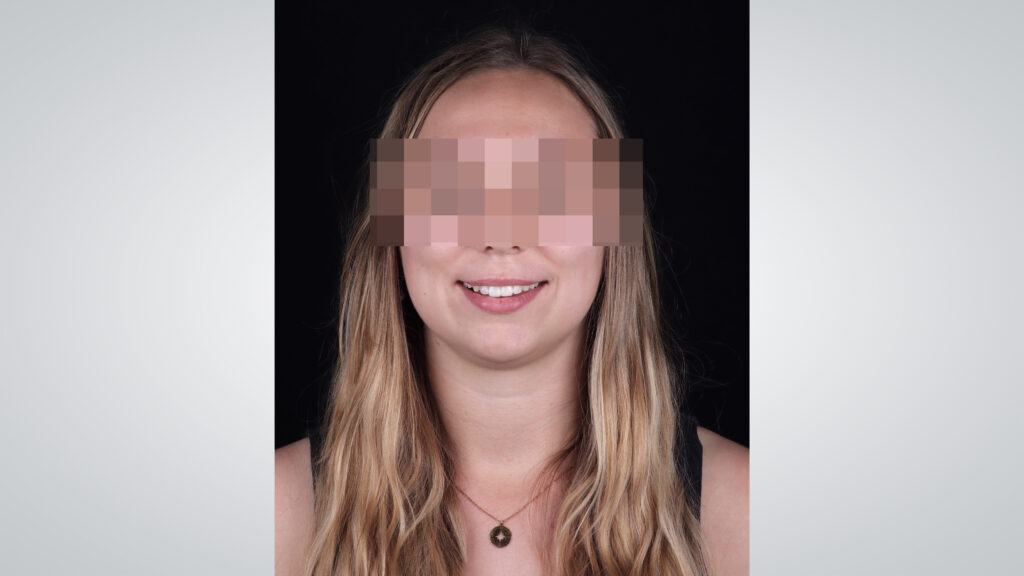

Jeder Patient ist einzigartig. Daher steht am Beginn einer Behandlung die umfassende Analyse. Oftmals liegt der Fokus nur auf den Zähnen. Doch es sind nicht nur Zahnform und -farbe, die das Lächeln eines Patienten definieren. Erst das Zusammenspiel von Gesicht, Lippen, Zahnfleisch, Zähnen etc. ergibt das harmonische Gesamtbild. Insbesondere bei der ästhetischen Rehabilitation ist es wichtig, mit einer ästhetischen Analyse zu beginnen (Abb. 3). Das Gesicht ist wie ein offenes Buch und gibt uns viele Informationen, z. B. über Malokklusion und über symmetrische Verhältnisse. Zu den wichtigen Ästhetik-Parametern gehören untere anderem die extraorale Mittellinie, die interpupilläre Linie und die interkommisurale Linie.

Im vorliegenden Fall wurde eine leichte extraorale Verschiebung der Mittellinie nach links festgestellt. Zudem zeigte die interkommisurale Linie eine Diskrepanz von links nach rechts. Bemerkenswert war die signifikante Volumendifferenz der rechten Lippenpartie im Vergleich zur linken. Zudem wurde eine Abweichung zwischen extraoraler und intraoraler Mittellinie identifiziert. Die klinische Befundung ergab einen Engstand im Oberkiefer, welcher als Rezidiv nach einer kieferorthopädischen Behandlung interpretiert wurde. Zusätzlich wurden ein Zahnschmelz-Chipping, eine Kunststoffverblendung am endodontisch vorbehandelten Zahn 11 sowie ein mild ausgeprägtes Gummy Smile diagnostiziert; insgesamt zunächst ein vergleichsweise einfacher Fall für ein Aligner-Bleaching-Veneers-Konzept. Aber: Obwohl der Fall auf den ersten Blick wie ein einfacher „Kandidat“ für ein Aligner-Bleaching-Veneers-Konzept wirkte, offenbarte eine detaillierte Untersuchung des Unterkiefers die volle Komplexität. Die Unterkieferfront zeigte eine blockartige Verschiebung. Während die rechte Seite intrudiert und nach bukkal protrudiert war, zeigte die linke Seite eine Extrusion und Retrusion (Abb. 4). Diese spezifische Konstellation erklärte die in der ästhetischen Analyse festgestellte Lippenposition. Ursache für die Situation war ein fehlerhaft positionierter Retainer. Der Retainer am rechten Eckzahn war vor Jahren abgebrochen. Das verursachte diese negative Entwicklung bei einer ansonsten positiven Retainer-Funktion. Die Blockbewegung des Unterkiefers musste auf diesen Umstand zurückgeführt werden.

Die Reise der Patientin, die mit dem Traum begann, an ihrem Hochzeitstag mit einem perfekten Lächeln zu strahlen, war abgeschlossen (Abb. 15). Am Ende sehen wir eine glückliche junge Frau mit einem Lächeln, das von Herzen kommt. Auch aus Sicht der Zahntechnik ist ein solches Lächeln immer die schönste Art, anderen die Zähne zu zeigen. Es ist das Ergebnis von Teamarbeit, Präzision und dem Wunsch, immer das Beste für den Patienten zu erreichen. Die Geschichte endet hier, doch das strahlende Lächeln der Patientin wird sicherlich noch viele Jahre bestehen. Ihre Reise dahin war nicht nur ein technischer Prozess, sondern eine emotionale Erfahrung, die von Vertrauen und einem gemeinsamen Ziel geprägt war. Und so ist diese Geschichte ein lebendiges Beispiel dafür, wie Kunst, Wissenschaft und Emotionen in der Zahnmedizin zu einem harmonischen Ganzen verschmelzen können. Ein Lächeln, das nicht nur die Schönheit der Zähne zeigt, sondern auch die Geschichte und die Emotionen dahinter.